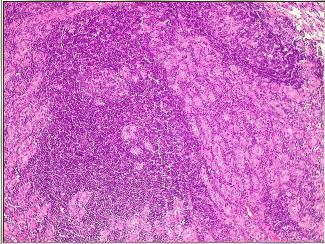

Necrose Caseosa no Linfonodo

Nas lâminas de cima percebemos que o tecido linfóide normal diminui devido as áreas de necrose caseosa. Embaixo, vemos o granuloma com suas células caracterísitcas: células gigantes do tipo Langhars (ferradura) e células epitelióides

Seta Amarela: Cèlulas Epitelióides. Células Verdes: Gigantócito tipo Langhans (com seus núcleos organizados na periferia- tipo ferradura)

Granuloma de células epitelióides gigantes na tuberculose no linfonodo

Seta de cima: Necrose caseosa no centro do granuloma, Seta de baixo: Gigantócitos do granuloma

Necrose Caseosa (coagulativa) em destaque, com granulomas apontados pelas setas

Célilas epitelióides (são as células que definem o granuloma) e gigantócito (do tipo Langhans) com núcleo organizado em ferradura na periferia (diferente da de corpo estranho que tem núcleos centrais desorganizados)